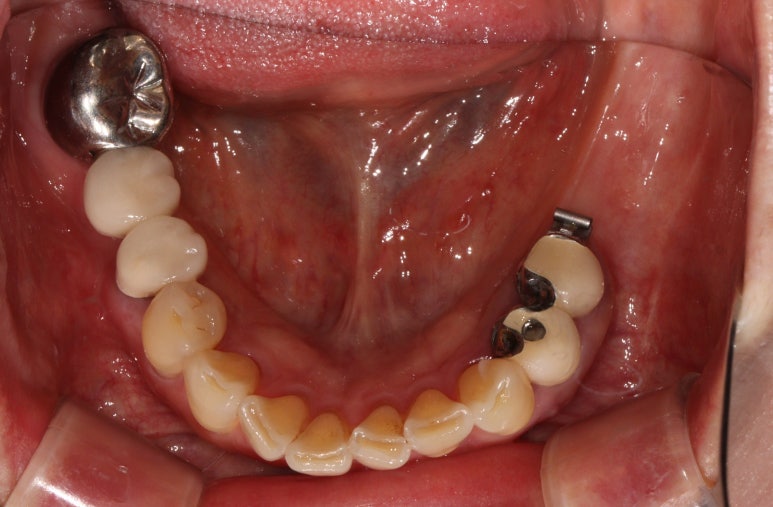

임플란트 2차수술 (3달 경과 후)

- 유리치은이식술 (free ginigval graft)

임플란트 1차수술을 마치고 정확이 3개월 뒤에 임플란트 2차수술을 시행하였습니다.

임플란트 2차수술을 하는 바로 이 시기가 유리치은이식술 (FGG)을 하기에 가장 좋은 시기입니다.

먼저 부분층 판막 (partial thickness flap)을 예쁘게 형성하여,

골막이 드러나는 환경을 만들어 줍니다.

원하는 크기를 선택하여 치유지대주를 연결해 줍니다.